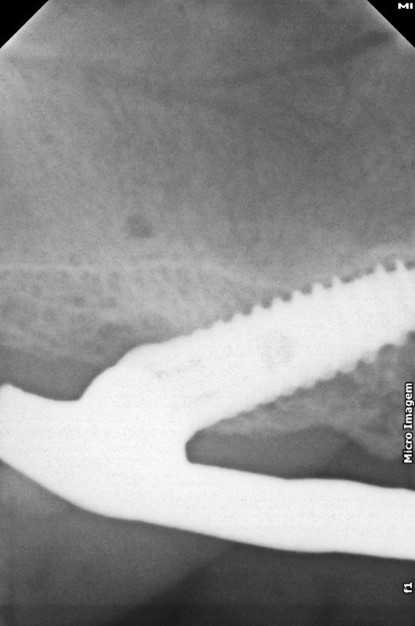

Fig. 2 – Radiografia inicial

Na análise radiográfica, constatou-se pneumatização do seio maxilar direito em direção ao pilar canino. No lado esquerdo, a extensão da pneumatização poderia inviabilizar a realização da técnica sem enxertos ósseos. Para garantir a instalação precisa e segura do implante, foi realizado um acesso lateral à janela do seio maxilar, permitindo o tratamento da parede anterior do seio com uma sonda para determinar a posição ideal do implante distal. Aproveitou-se o máximo de osso disponível, tangenciando o seio maxilar e eliminando a necessidade de enxertos ósseos. Foi escolhido o sistema Vezza da FGM, devido a geometria que fornece alta estabilidade primária e oferece conexão hexagonal externa universal, ou seja, bastante versátil.